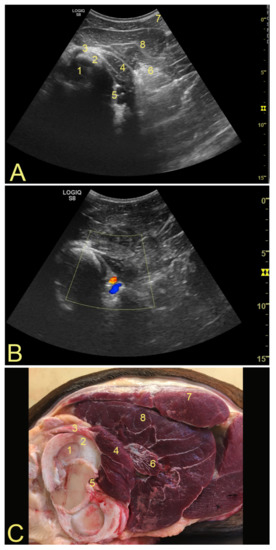

3.1. Anatomical Landmarks for Probe Positioning and Technical Settings

3.2. Popliteal Complex Characteristics